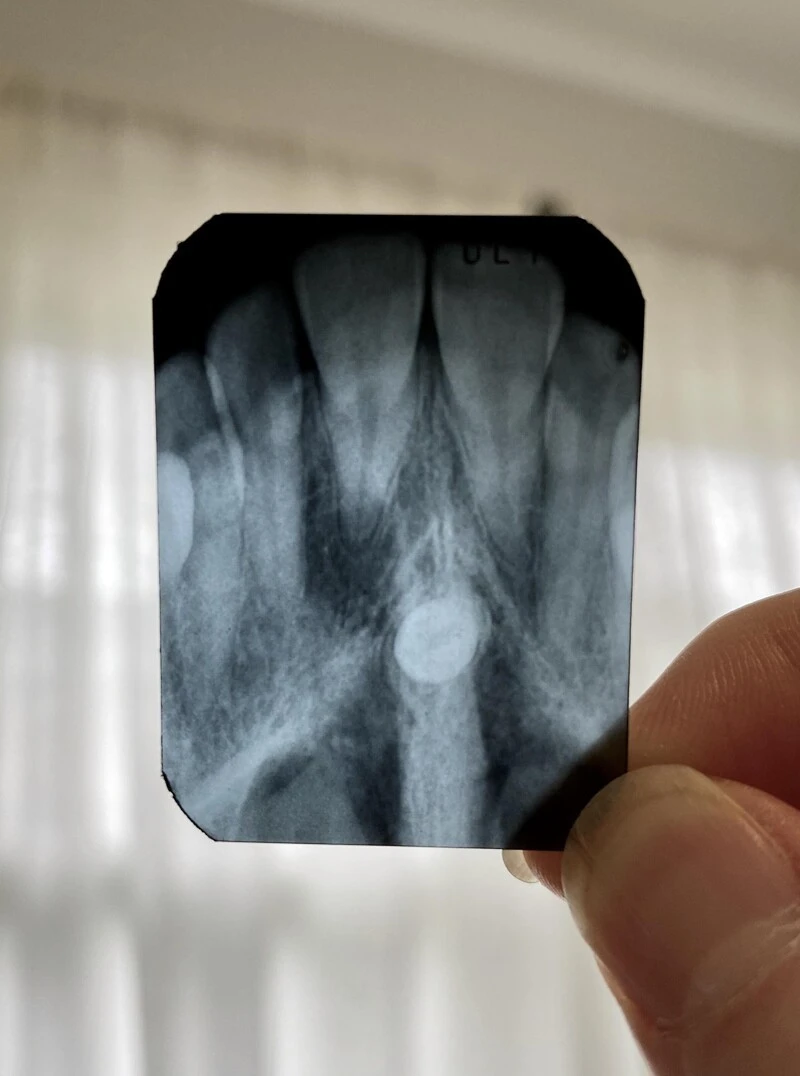

"У меня на нёбе начал расти зуб. Сегодня его удалили"